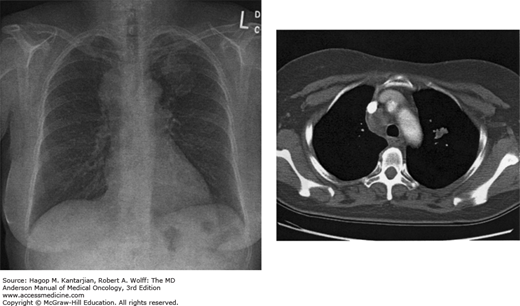

Stage IIIB non–small cell lung cancer (NSCLC). This patient presented with chest pain, and the chest x-ray (left) showed an approximately 4.0- by 3.0-cm mass in the left upper lobe and an additional mass in the right mediastinum. Initial computed tomography (CT) revealed a 4.5-cm mass in the left upper lobe and a 5-cm mass in the paratracheal region. Biopsy confirmed NSCLC. Staging evaluation showed no distant metastatic disease (T2N3M0). The patient was treated with concurrent chemotherapy and radiotherapy. The posttreatment CT (right) showed significant therapeutic response.